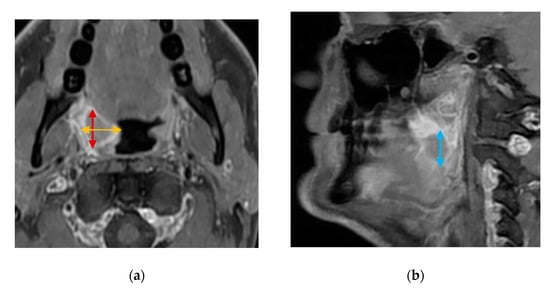

CTs and MRIs will be evaluated for the greatest tumor diameters in three dimensions (craniocaudal, anteroposterior, and mediolateral) for visible tumors. Tumors will be measured in three perpendicular dimensions in axial (anteroposterior and mediolateral diameters) and coronal/sagittal planes (craniocaudal diameter) (Figure 4). A categorical T-stage will be estimated using CT and MRI according to the UICC8 staging system.

Figure 4. Contrast-enhanced, T1-weighted MRI images of a stage T1 squamous cell carcinoma of the right palatine tonsil: (a) axial orientation showing the mediolateral (yellow bi-directional arrows) and anteroposterior (red bi-directional arrows) diameters of the tumor; (b) sagittal orientation showing the craniocaudal (blue bi-directional arrows) diameter of the tumor.